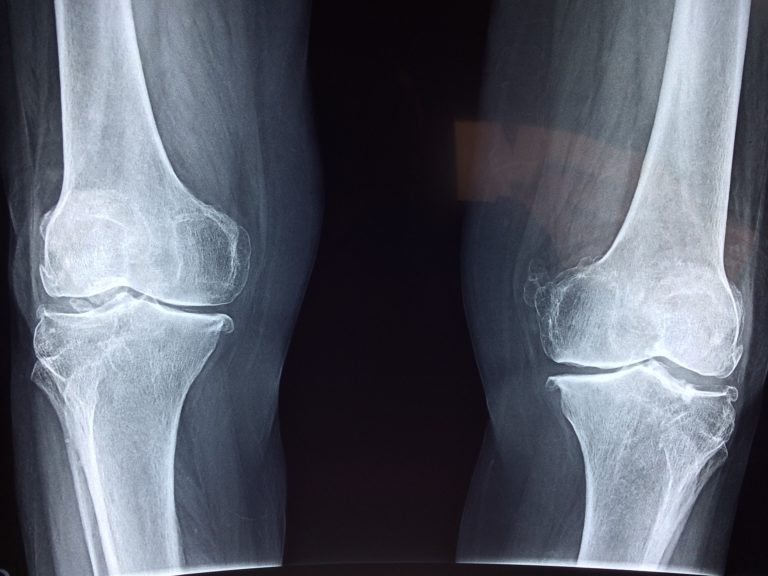

Opuchnięte kolano może być sygnałem różnych problemów zdrowotnych. W takim przypadku konieczna jest wizyta u lekarza, jeśli stan nie ustępuje lub się pogarsza. Przedstawiam mój sprawdzony domowy przepis, który pomaga na ból, obrzęk i nawet zalegającą wodę w kolanie. Jest prosty w przygotowaniu.